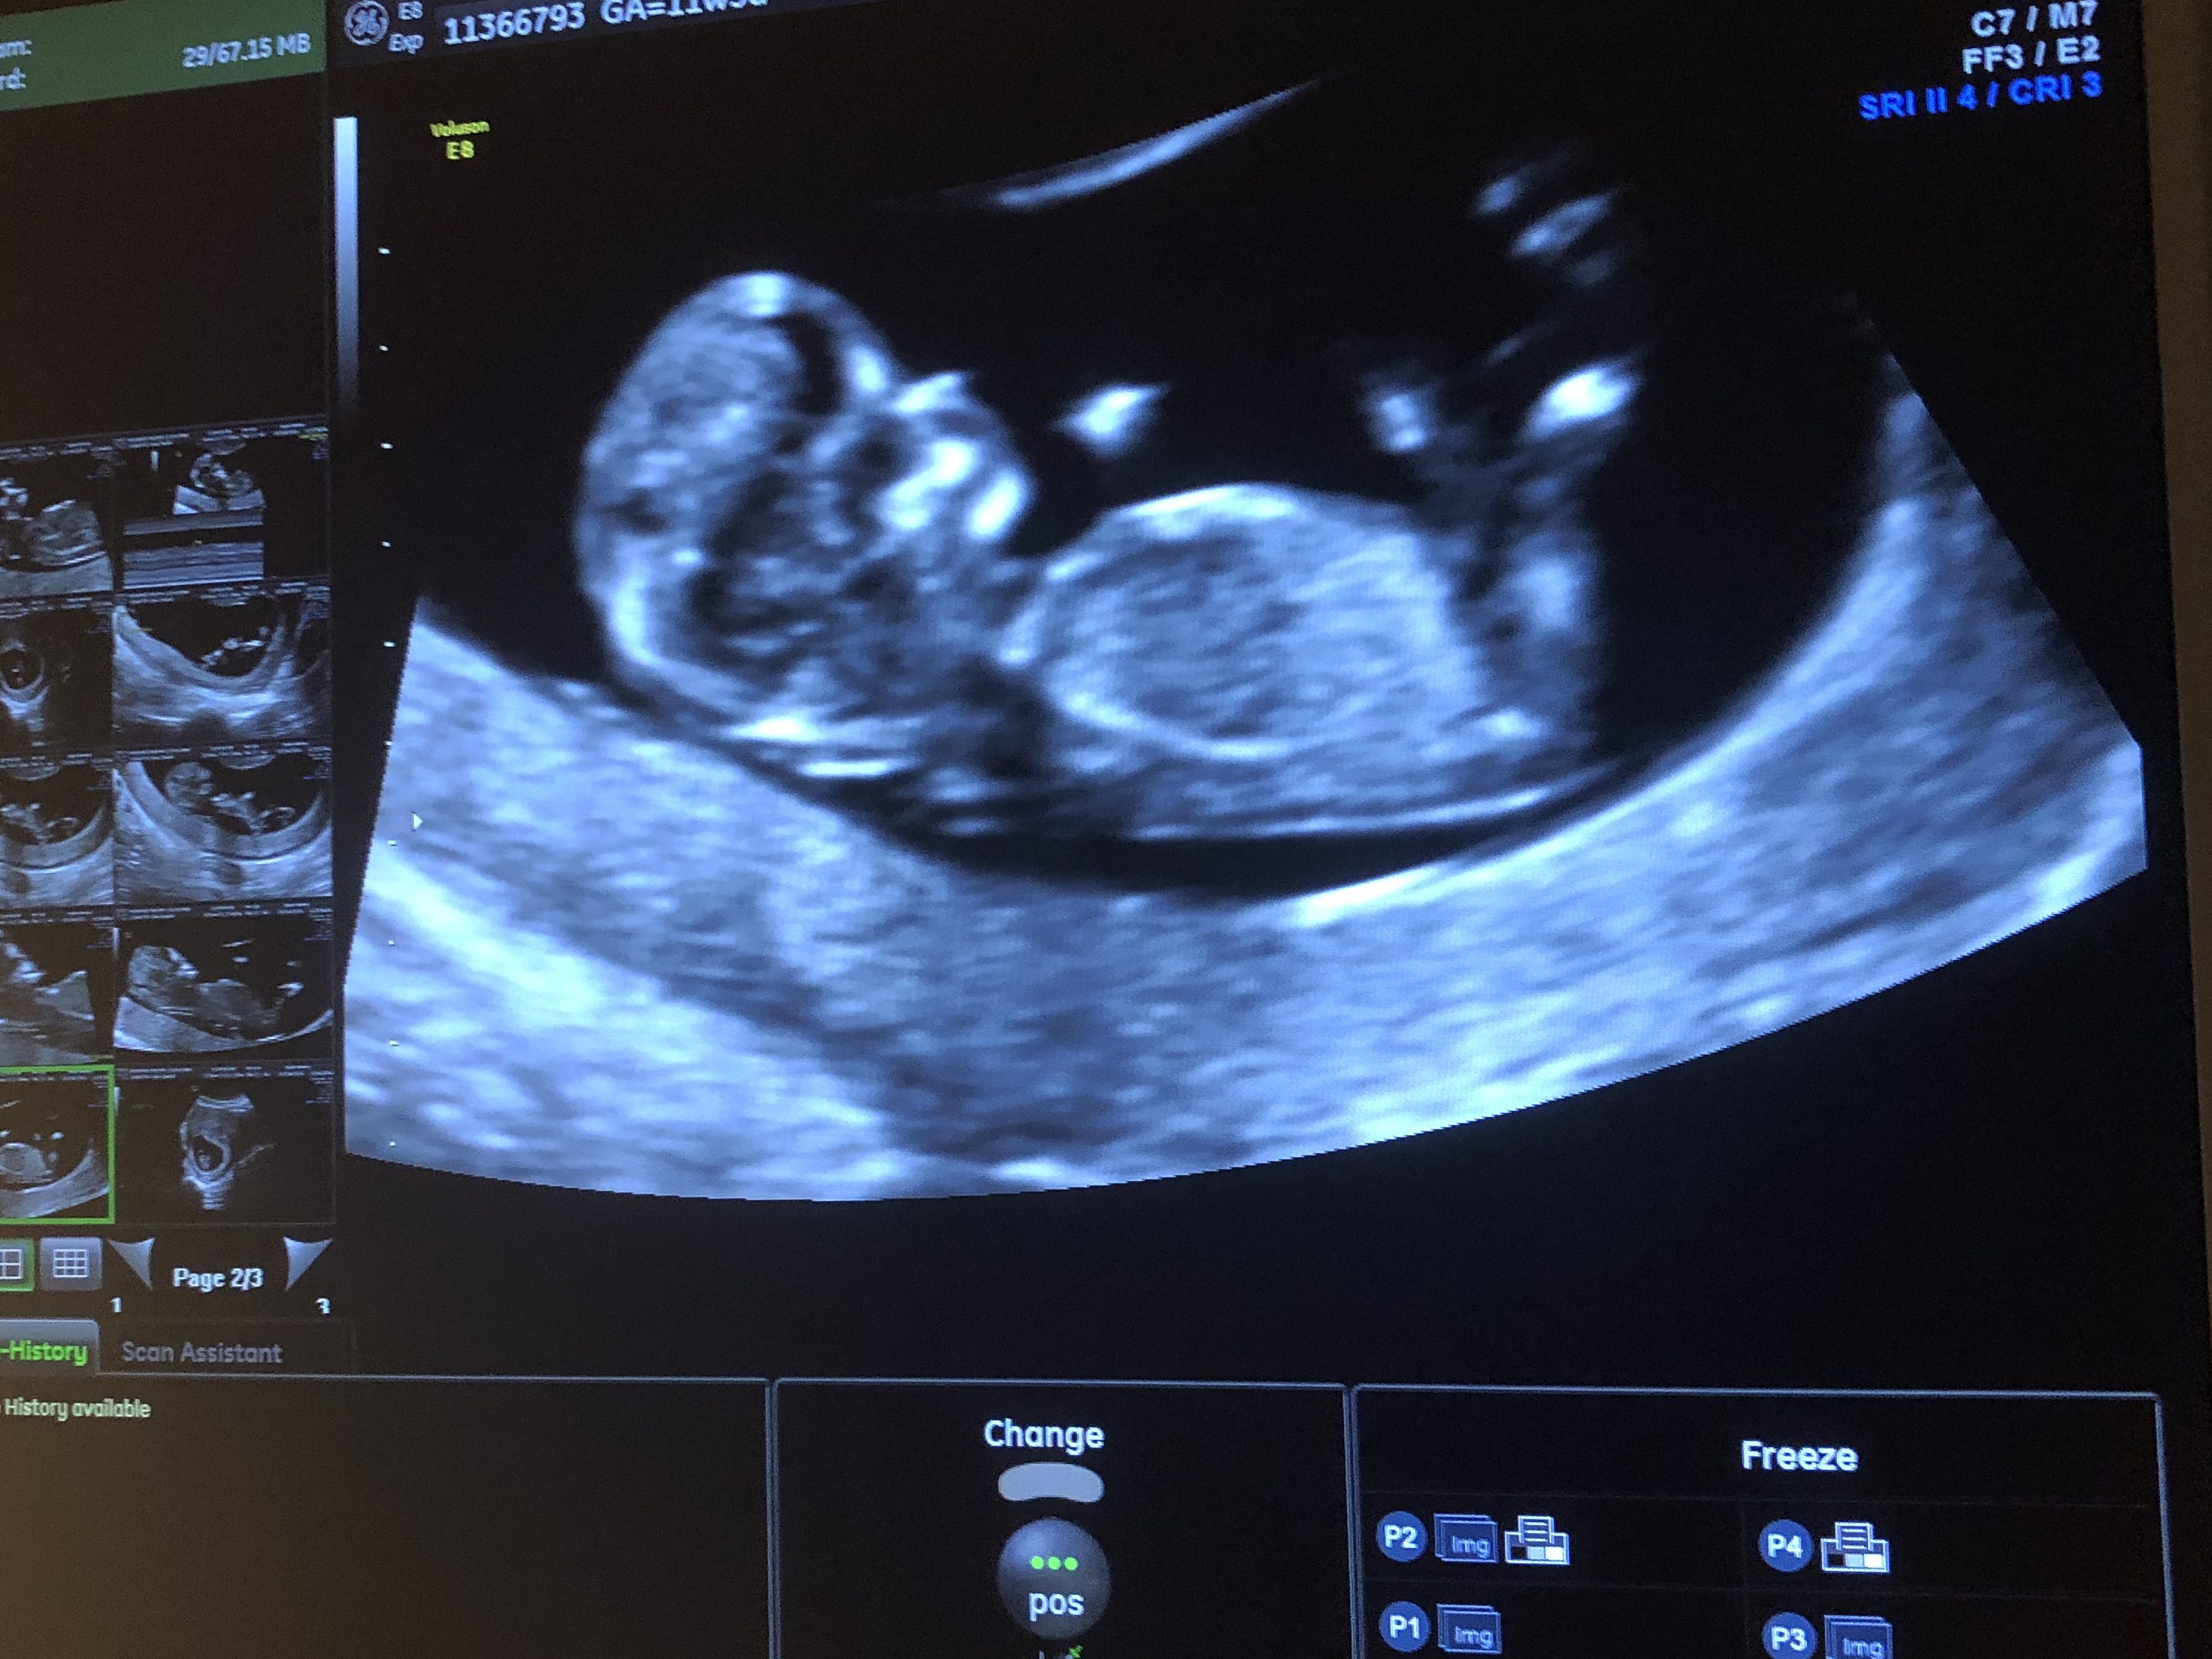

After 30 weeks gestation, I had biweekly ultrasounds to check on the previa and at 34 weeks, the radiologist told me that it was very unlikely the previa would resolve because my cervix was still mostly covered by the placenta. She suggested I go ahead and schedule my C-section at 37 weeks gestation (they don’t want women with unresolved placenta previa to go into labor naturally so they generally schedule a C-section in the 37th week because chances of spontaneous labor occurring after 37 weeks are high) but told me I had the choice of giving it one last look with an ultrasound at 36 weeks. It was highly doubtful the placenta would move much this late in pregnancy, she warned, but I jumped on the opportunity and schedule the final ultrasound. There was no harm in checking (I say this because I had health insurance to cover the cost of these ultrasounds), I thought, and in the unlikely chance it is resolved, I’d get to avoid an unnecessary C-section. What did I have to lose?

Thank goodness I opted for the ultrasound because by 36 weeks the placenta was no longer obstructing my cervix and I was given the green light for a natural delivery! It was a miracle! We were all so surprised, including the radiologist and my midwife.